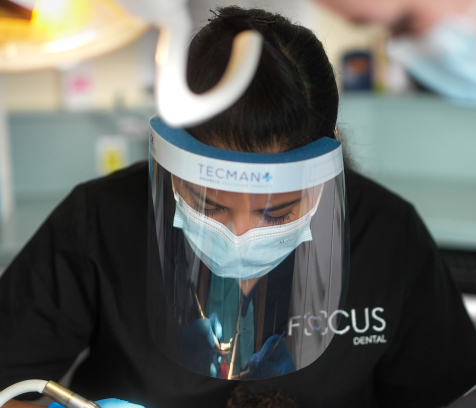

At our Southend-on-Sea and Westcliff-on-Sea practices, composite bonding uses tooth-coloured resin to sculpt and restore your smile in a single visit.

In our calm, modern clinics, our specialist-led team delivers personalised, confidence-boosting results that preserve your natural teeth.

Resin application

Tooth-coloured resin is layered and sculpted to the perfect shape.

Gentle techniques in serene, modern surroundings